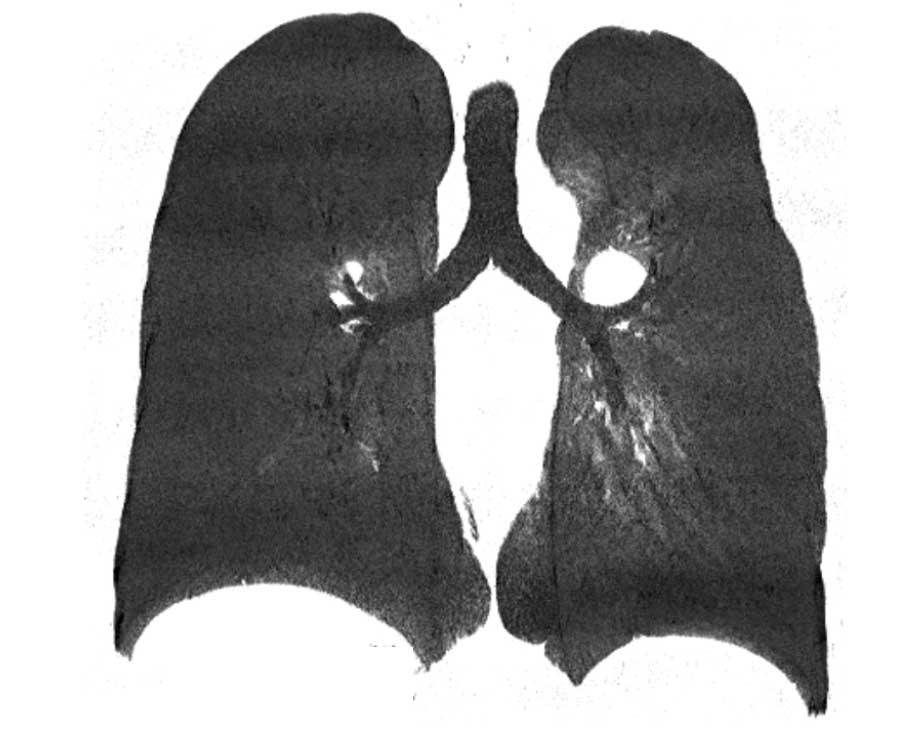

Hình ảnh MinIP (chiếu cường độ tối thiểu) lát dày trong đồng phân trái ở nữ giới 54 tuổi mắc bệnh tim bẩm sinh, cho thấy giải phẫu phế quản đối xứng với hình ảnh ‘hai phổi trái’.